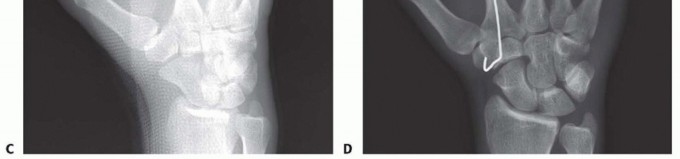

Clinical & Radiographic Imaging Archive